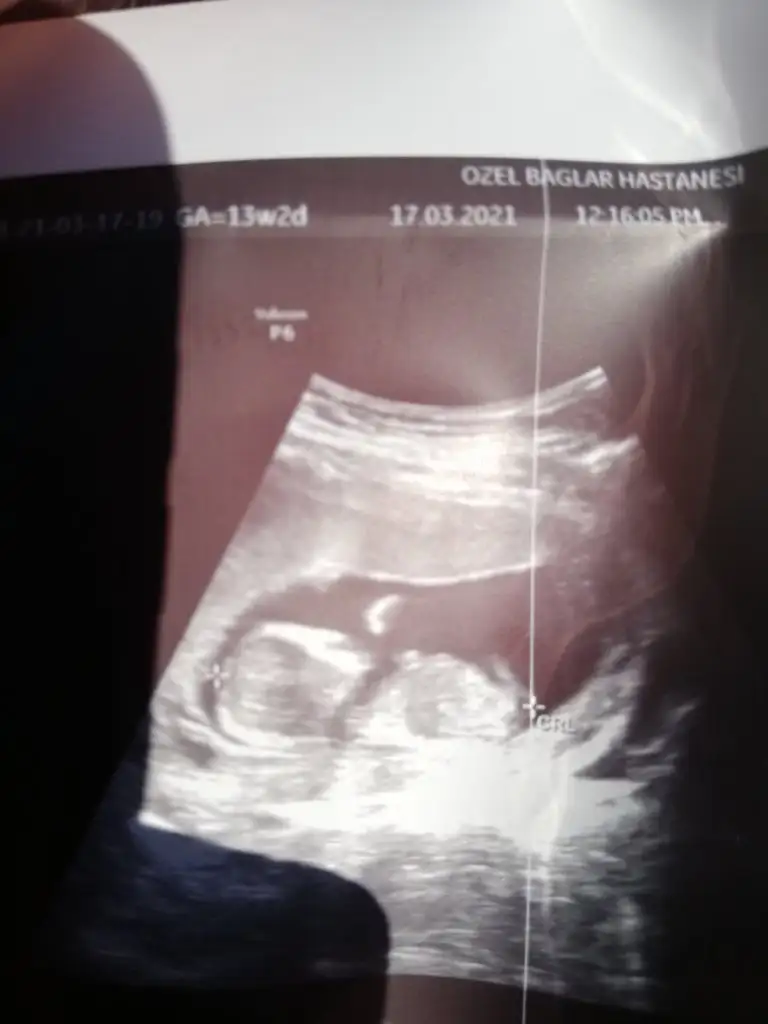

Ikra meyra Ikra meyra tahminin doğru çıktı 16 hafta erkek demiştin doktorum kesin erkek elbiselerini bile al dedi ☺ değişir mi bilmiyorum ama atıyim bir bak

Artık erkektir canım 😍 sağlıkla gelsin oğlusun 🥰 anketim oylarsaniz sevinirim 😘